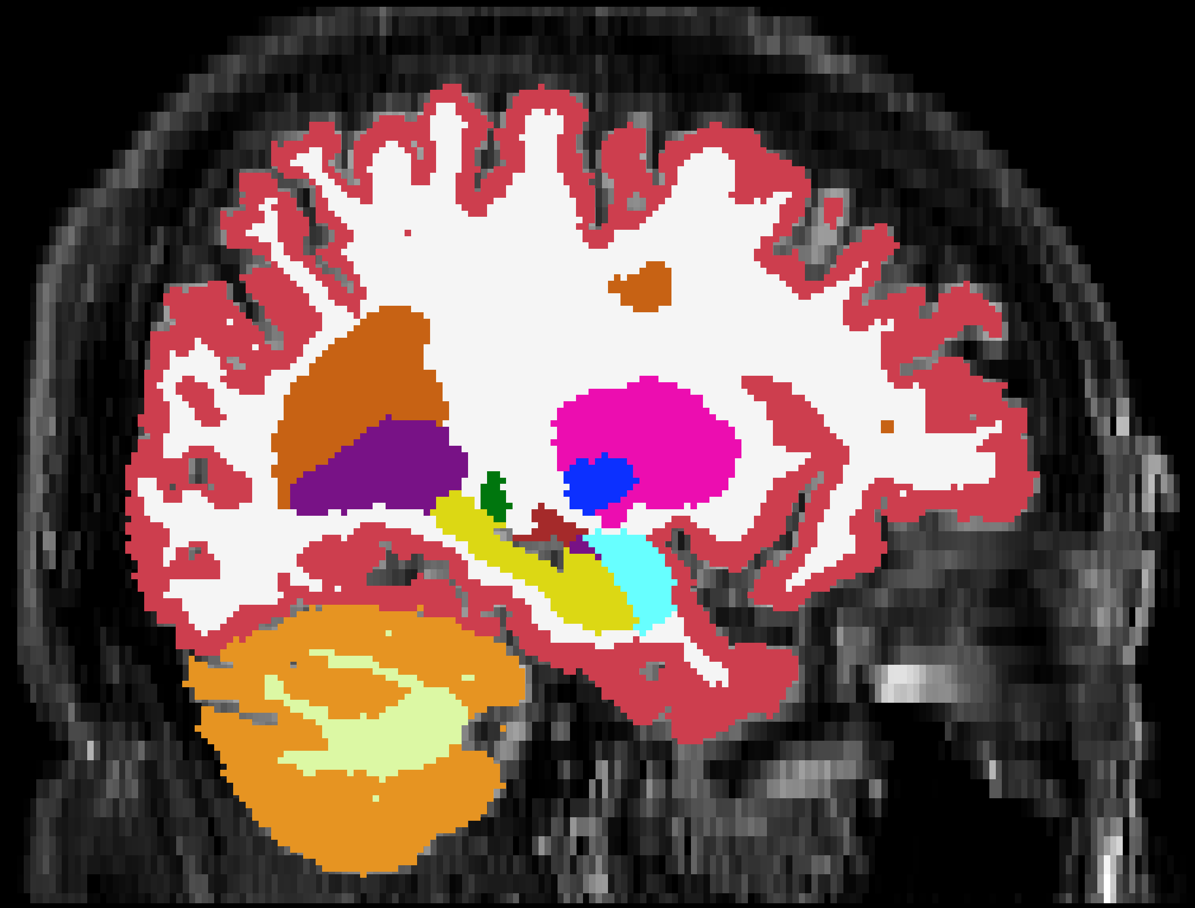

Brain atrophy and white matter hyperintensity (WMH) are critical neuroimaging features for ascertaining brain injury in cerebrovascular disease and multiple sclerosis. Automated segmentation and quantification is desirable but existing methods require high-resolution MRI with good signal-to-noise ratio (SNR). This precludes application to clinical and low-field portable MRI (pMRI) scans, thus hampering large-scale tracking of atrophy and WMH progression, especially in underserved areas where pMRI has huge potential. Here we present a method that segments white matter hyperintensity and 36 brain regions from scans of any resolution and contrast (including pMRI) without retraining. We show results on six public datasets and on a private dataset with paired high- and low-field scans (3T and 64mT), where we attain strong correlation between the WMH ($\rho$=.85) and hippocampal volumes (r=.89) estimated at both fields. Our method is publicly available as part of FreeSurfer, at: http://surfer.nmr.mgh.harvard.edu/fswiki/WMH-SynthSeg.